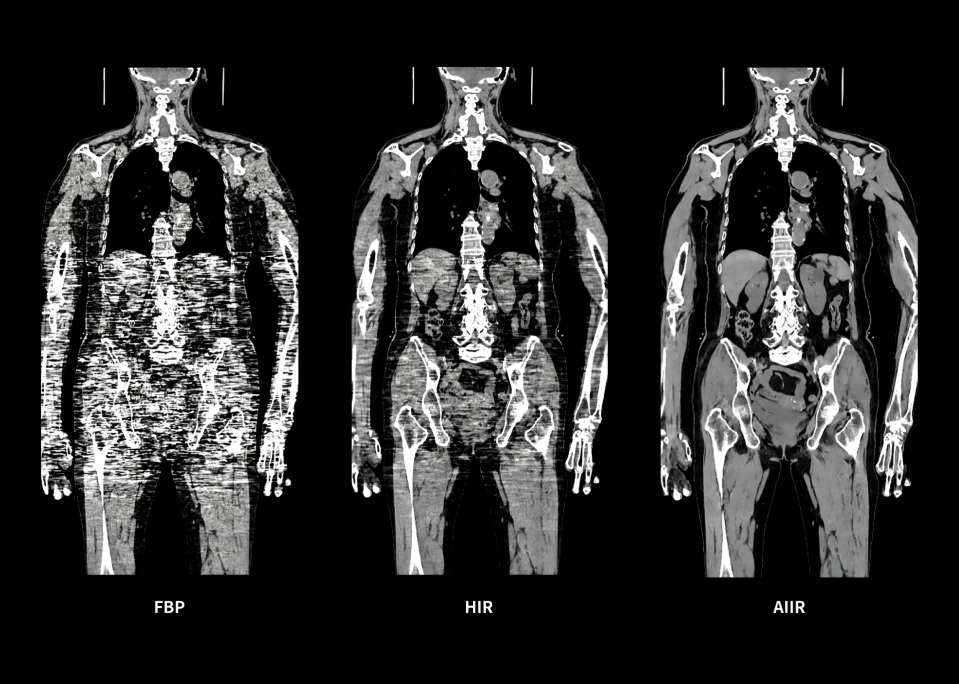

AIIR* – AI Iterative Reconstruction

Throughout the iterative loop of forward and backward projection between the raw data domain and the image domain, AIIR consistently takes into account the accurate modeling of optics, noise, anatomy, and physics statistics. Additionally, AIIR integrates deep learning-based de-noising technology, supplanting the conventional regularization role of MBIR in the optimization reconstruction process.

In brief, AIIR utilizes deep learning-based AI technology to attain robust noise reduction and natural image texture, while incorporating MBIR technology to achieve precise anatomical structure representation and artifact suppression. This technique surpasses the limitations of using either MBIR or deep learning reconstruction (DLR) independently.